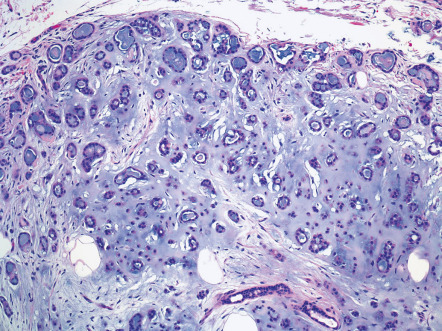

Pathology

At low magnification, fibrofolliculoma displays slender strands of follicular mantle cells that emanate from a folliculosebaceous unit at the level of the isthmus ( Fig. 111.4C ). Usually, the strands are composed of cells with a slightly basaloid appearance, and sometimes, tiny integrated collections of mature sebocytes are identifiable. The epithelial component may assume a mitt-like morphology in some instances, encasing the vascularized fibrous stroma.

Perifollicular fibroma consists almost exclusively of stroma that is identical to the stromal elements of fibrofolliculoma and angiofibroma. Lesions consist of spindled and stellate cells arrayed concentrically around follicles and distributed amongst thickened collagen bundles with a proportionate number of intervening small thin-walled vessels. Sometimes, a concurrent component of follicular epithelial hyperplasia is identifiable, although the epithelium tends to be inconspicuous in comparison to fibrofolliculoma. Trichodiscoma was thought by Pinkus to represent a unique proliferation with differentiation toward the haarscheibe (hair disk), which is probably a mythical structure. More recently, trichodiscomas have been interpreted as fibrofolliculomas or perifollicular fibromas with myxoid rather than fibrous stroma. Lastly, the so-called neurofollicular hamartoma is now considered to be a type of trichodiscoma.